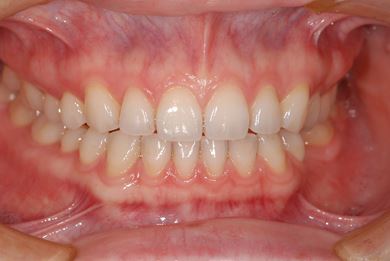

| 性別/年齢 | 女性 / 29歳 | ||||||||||||||||||||||||||||||||

| 主訴 | インプラント治療と、親知らずの抜歯の相談。なるべく安価で、短期間で終了して欲しい。 | ||||||||||||||||||||||||||||||||

| 治療方針 | 欠損部分をインプラント治療にて、機能的・審美的回復を行う。 | ||||||||||||||||||||||||||||||||

| 治療内容 | インプラント1本、メタルボンドセラミッククラウン1本 | ||||||||||||||||||||||||||||||||

| 総治療費 | 252,000円 | ||||||||||||||||||||||||||||||||

| 治療期間 | 11ヶ月 |